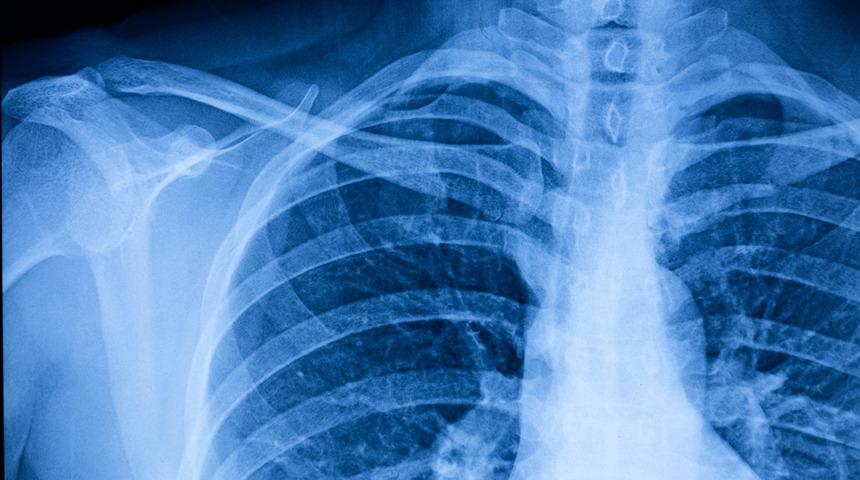

Ciddi kazalar sonucu oluşan tramvatik yelken göğsü, akciğerde ciddi komplikasyonlara sebep olabilmektedir. Ciddi kaza geçiren hastanın mutlaka doktora görünmesi gerekmektedir. Doktor tarafından fiziki muayene yapılmasının ardında travmatik yelken göğsü teşhisi konulabilmektedir. Göğüs duvarının nefes alırken nefese bağlı olarak hareket etmemesi ve anormal bir şekilde hareket etmesi hastalığın en belirgin semptomudur. Fiziki muayene sonrasında doktor yelken göğsünden şüpheleniyorsa tanıları doğrulamak için X ışını kullanır. Travmatik yelken göğsü genellikle röntgen ile kesin tespit edilebilen ve teşhisi konulabilen bir hastalıktır.